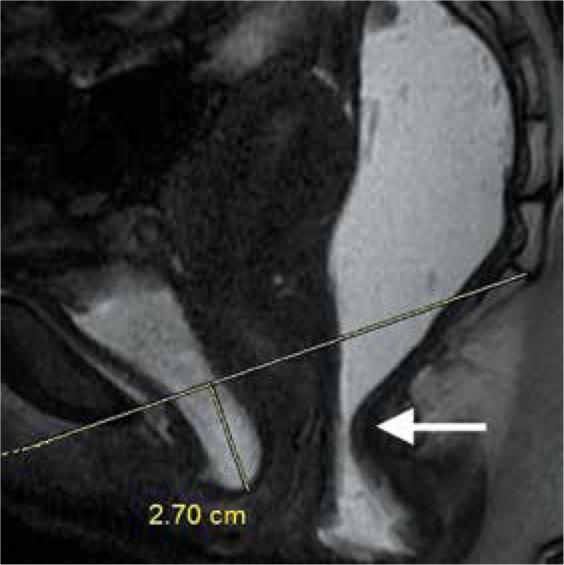

Magnetic resonance defecography findings of dyssynergic defecation.

Dyssynergic defecation (DD) is defined as paradoxical contraction or inadequate relaxation of the pelvic floor muscles during defecation, which causes functional constipation. Along with the anal manometry and balloon expulsion tests, magnetic resonance (MR) defecography is widely used to diagnose or rule out pelvic dyssynergia. Besides the functional abnormality, structural pathologies like rectocele, rectal intussusception, or rectal prolapse accompanying DD can also be well demonstrated by MR defecography. This examination can be an uncomfortable experience for the patient, so the imaging method and the importance of patient cooperation must be explained in detail. The defecatory phase of the examination is indispensable for evaluation, and inadequate effort should be ruled out before diagnosing DD. MR defecography provides important data for the diagnosis of DD, but optimal imaging criteria should be applied. Further tests can be suggested if patient co-operation is not sufficient or MR defecography findings are irrelevant.

排便协同失调(DD)被定义为排便时盆底肌肉反常收缩或松弛不足,从而导致功能性便秘。除肛门测压法和气囊排出试验外,磁共振(MR)排粪造影术也被广泛用于诊断或排除盆腔协同失调。除了功能异常外,MR排粪造影术还能很好地显示伴随DD出现的诸如直肠膨出、直肠套叠或直肠脱垂等结构病变。这项检查对患者来说可能是一次不舒服的体验,因此必须详细解释成像方法以及患者配合的重要性。检查的排便阶段对于评估不可或缺,在诊断DD之前应排除用力不足的情况。MR排粪造影术为DD的诊断提供了重要数据,但应采用最佳成像标准。如果患者配合不充分或MR排粪造影结果不相关,则可建议进一步检查。